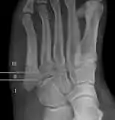

Anatomy of the fifth metatarsal.

3 zone description

2 zone description